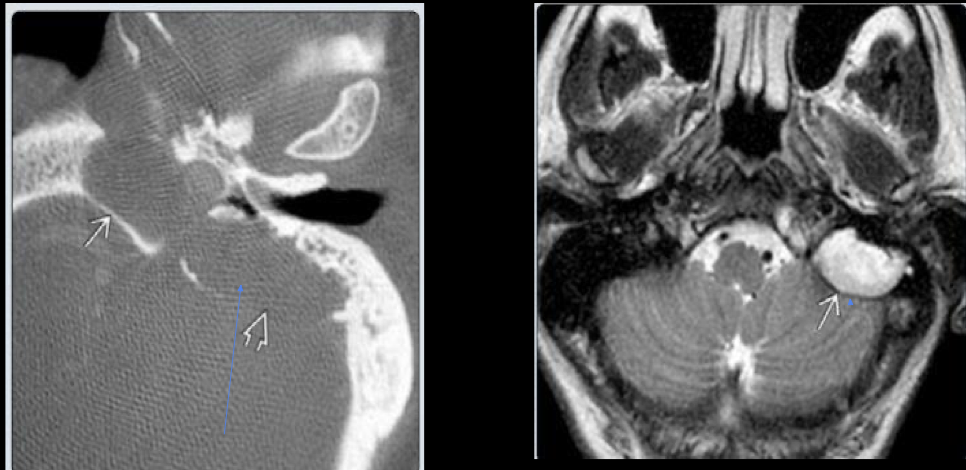

14

A

RM Colesteatoma

15